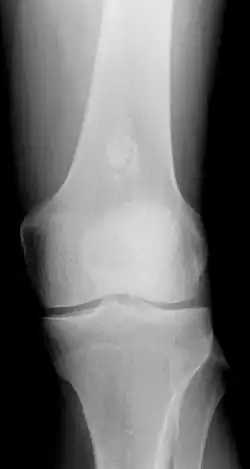

- X-ray – On plain film, an enchondroma may be found in any bone formed from cartilage. They are lytic lesions that usually contain calcified chondroid matrix (a "rings and arcs" pattern of calcification), except in the phalanges. They may be central, eccentric, expansile or nonexpansile.

Differentiating an enchondroma from a bone infarct on plain film may be difficult. Generally, an enchondroma commonly causes endosteal scalloping while an infarct will not. An infarct usually has a well-defined, sclerotic serpentine border, while an enchondroma will not. When differentiating an enchondroma from a chondrosarcoma, the radiographic image may be equivocal; however, periostitis is not usually seen with an uncomplicated enchondroma.